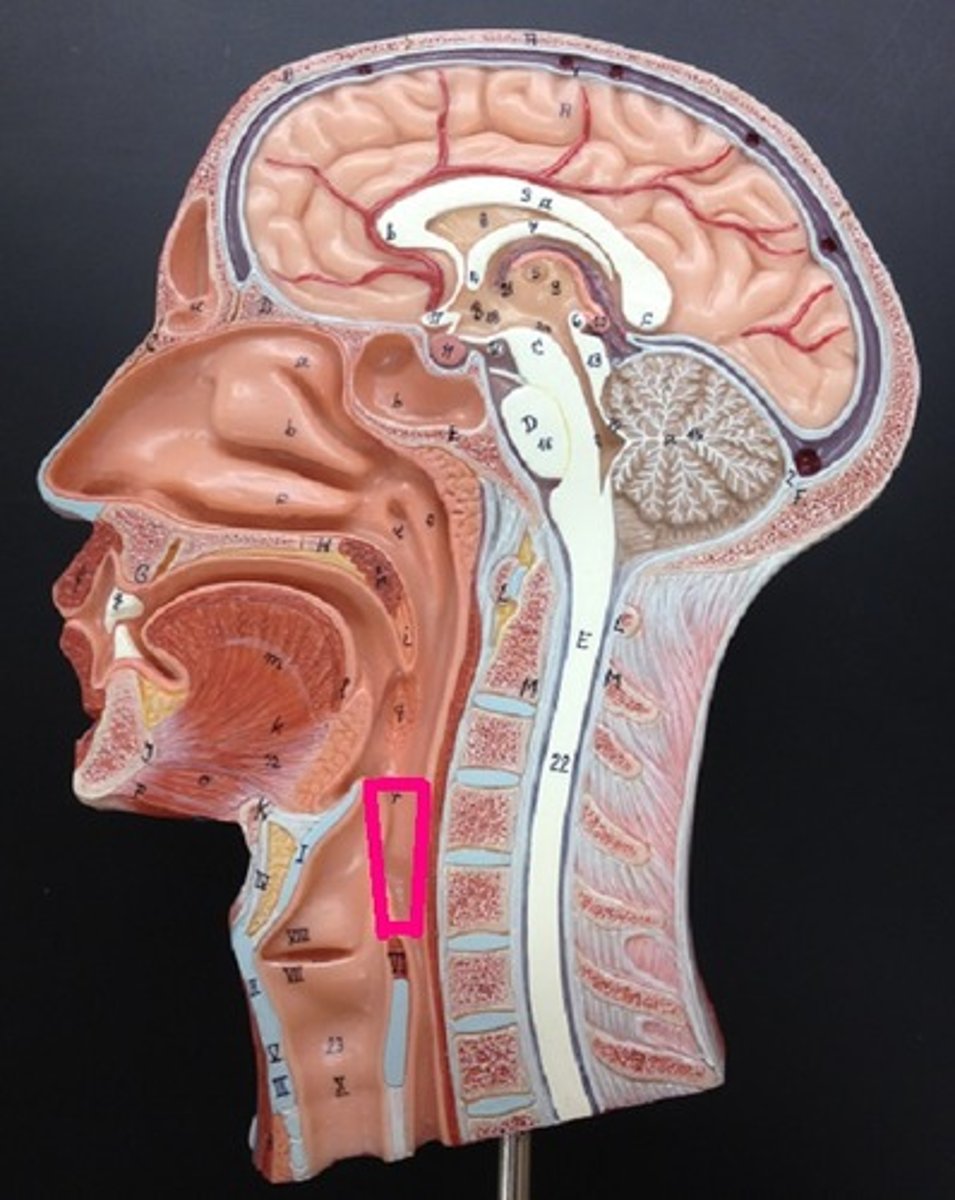

Pharynx

Esophagus

oropharynx

esophagus

Epiglottis

laryngopharynx